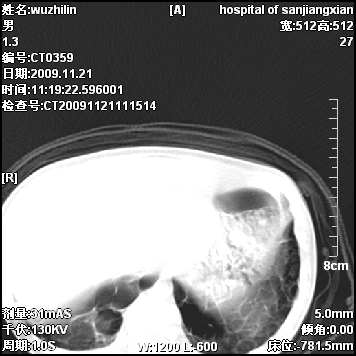

标题: PED3072: 1岁3个月患儿 胸部弥漫性病变 [打印本页]

标题: PED3072: 1岁3个月患儿 胸部弥漫性病变

两肺布满多个薄壁含气囊腔,以下肺居多,伴磨玻璃样密度影,左侧气胸。两肺发育不全、两肺多发肺囊肿并感染,其次考虑肺囊腺瘤。